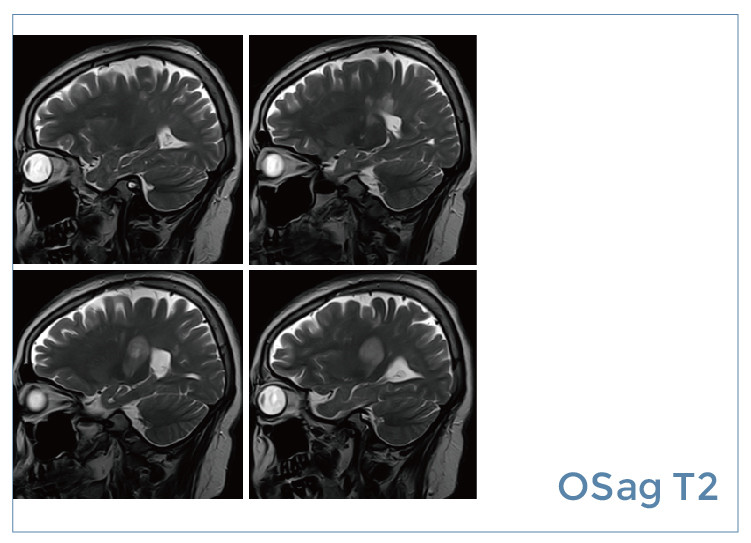

【朗润影像档案】20190823磁共振影像病例结果讨论